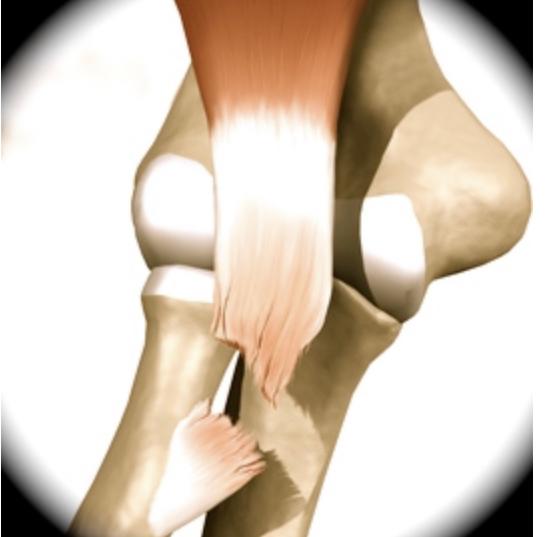

LESÃO DO BICEPS DISTAL

A LESÃO DO BICEPS DISTAL CONSTITUI-SE NA RUPTURA DO TENDÃO AO NIVEL DO COVELO. Acomete homens ao redor dos 30-50 anos, durante o movimento de flexão do cotovelo ao realizar o levantamento de algum peso. É comum sentir um estalo no momento da lesão evoluindo com perda de força. Existem diversos fatores de risco como tabagismo, uso de anabolizantes e doenças sistêmicas como o Lúpus. Ao exame físico apresenta dor na região anterior do cotovelo com inchaço e pode ficar roxo o local. Na maioria das vezes é possível observar uma deformidade em relação ao lado contra-lateral (encurtamento do tendão). O tratamento de escolha é cirúrgico para as lesões totais ou maiores que 50% do tendão. O tratamento conservador é de exceção, somente se o paciente for sedentário e de baixa demanda, pois se não tratado geralmente resulta em perda de força de supinação (±40%), de flexão (±30%) e a resistência.